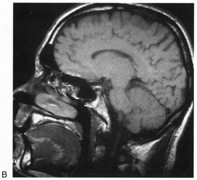

Achromatopsia in the contralateral hemifield alone can follow unilateral right or left occipital lesions (Fig. 18). Patients are typically asymptomatic until the defect is demonstrated on examination.234,235 Hemiachromatopsia is usually associated with a superior quadrantanopia;234,235,241 therefore, the color defect is only demonstrable in the remaining inferior quadrant. The preserved color vision in the ipsilateral hemifield allows normal or near-normal performance on centrally viewed tests of color vision such as pseudoisochromatic plates. The incidence of hemiachromatopsia is probably underestimated, given its asymptomatic nature and the failure of routine clinical color tests to detect its presence.

Fig. 18. Magnetic resonance imaging scan of patient with stroke causing a right hemiachromatopsia as well as partial superior quadrantanopia.